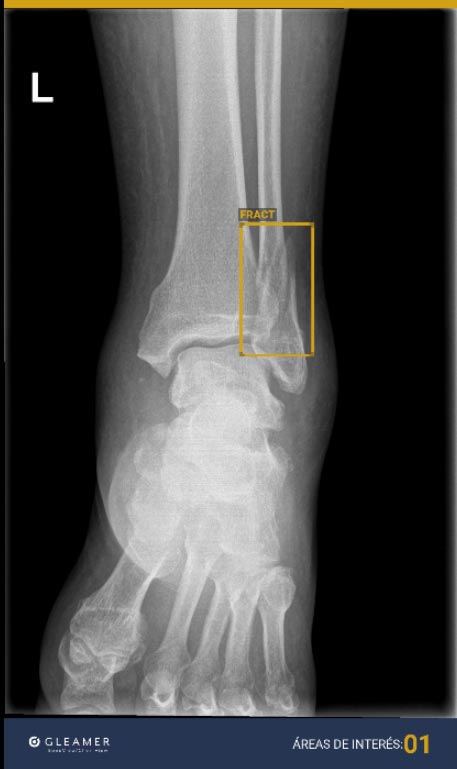

La IA está transformando el diagnóstico por imagen. Gracias a algoritmos avanzados, esta tecnología es capaz de reconocer patrones en las imágenes médicas que podrían pasar desapercibidos para el ojo humano, mejorando la toma de decisiones clínicas y logrando diagnósticos más precisos.

La IA actúa como un aliado clave para nuestros especialistas, optimizando la identificación de patologías y acelerando la generación de informes médicos. Con esta tecnología, somos capaces de detectar lesiones sospechosas con mayor exactitud, permitiendo iniciar los tratamientos adecuados con mayor rapidez.